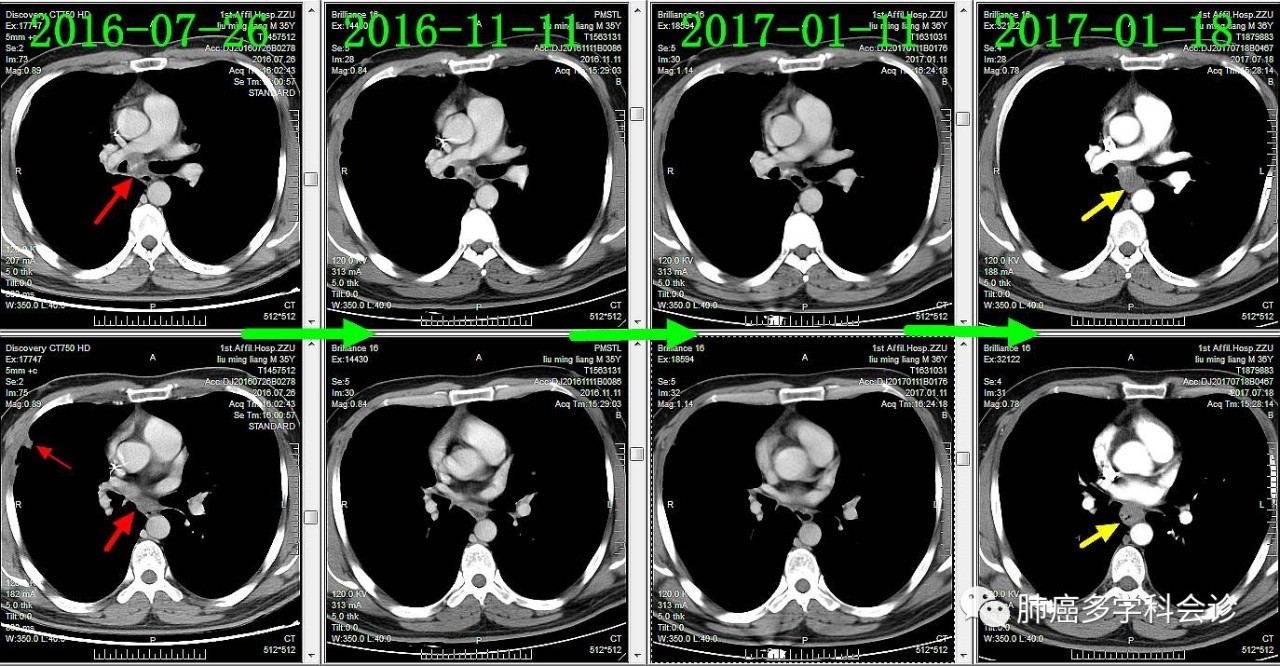

下面着重展现食管转移灶的发展过程。从2016-09-13(完成2个周期化疗)开始,上下两图分别为各时间点CT的上下两层:

食管不是肺癌的常见转移部位,容易被忽视。回顾该患者以往的胸部 CT 可见:在纵隔淋巴和原发灶逐渐退缩过程中,食管转移却逆势发展起来,反映了肿瘤对治疗反应的异质性。